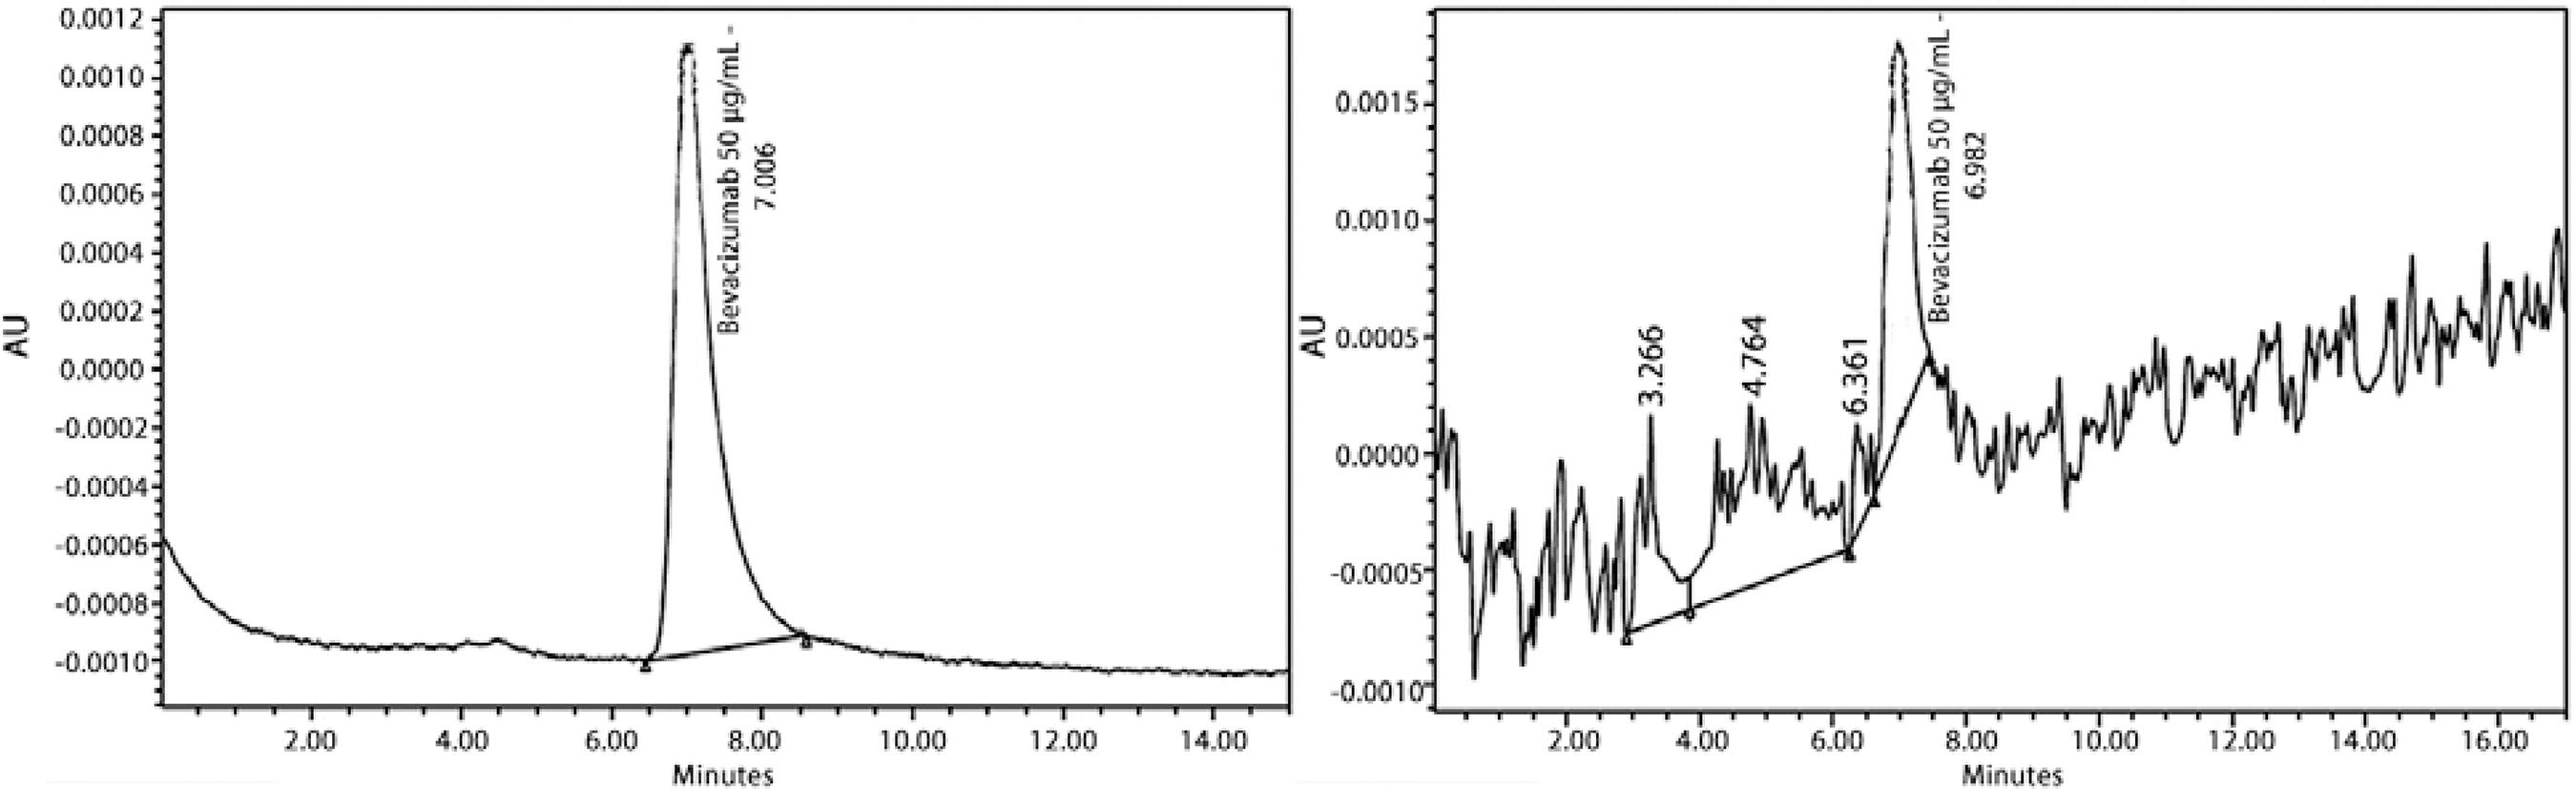

In order to detect free bevacizumab, five 0.5 ml samples of BMM were evaluated by size-exclusion high performance liquid chromatography (HPLC) using 50 µL of BMM with a flow rate of 1.0 mL/min, at 72 h (Waters BioSuite 250, 5 µm, HR SEC - 7.8 × 300 mm, pH 7.4, absorbance at 279 nm)(8). A HPLC column was used in which the mobile phase comprised PBS at a pH of 7.4. An ultraviolet detector (model 2487, Waters, USA) was used at a wavelength of 279 nm, and the area under peak was used to determine the quantity of the drug in the test solution.

HPLC detected bevacizumab in BMM at a mean retention time of 6.98 min across the five samples evaluated at 72 h (mean of 75.1% of free drug), close to the well-defined peak of free bevacizumab at 7.01 min (Figure 1)(5) BMM could be observed in the bleb areas of all patients during the first week (Figure 2). The blebs remained expanded with the hyaline material, but the liquid interface of aqueous humor could not be visualized during the slit-lamp examination.